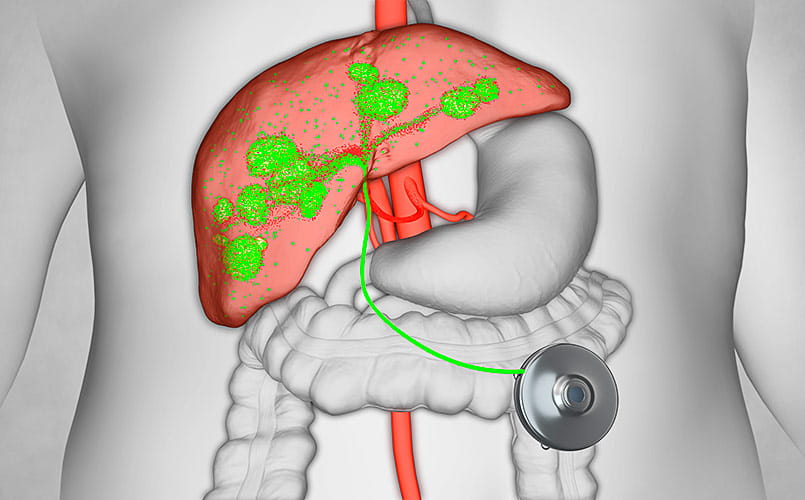

Hepatic artery infusion (HAI) therapy is a type of chemotherapy used to treat colorectal cancer liver metastases (colorectal cancer that has spread to the liver) and intrahepatic cholangiocarcinoma (cancer that occurs in the parts of the bile ducts that are inside the liver). HAI therapy is delivered through an implantable pump. More specifically, HAI therapy is indicated for:

HAI therapy has been in use for nearly 40 years. In that time, the therapy has shown to be effective at shrinking liver tumors in patients with unresectable CRLM and bile duct cancer, shrinking some tumors to the point where they can be surgically removed. For patients undergoing resection of CRLM (surgical removal of the tumor), HAI therapy in addition to surgery has been shown to reduce the likelihood of tumor recurrence within the liver.

- Unlike systemic chemotherapy, in which the anti-cancer drug enters the bloodstream and circulates throughout the body, HAI uses an implanted pump that delivers chemotherapy directly to the liver. The delivery of the drug directly to the liver tumor allows for achievement of up to 400 times higher drug concentration than is possible with traditional chemotherapy. The liver rapidly metabolizes 99 percent of the drug. This precise targeting minimizes toxic side effects to the rest of the body.

In HAI therapy, a device called the Intera 3000 Hepatic Artery Infusion Pump is implanted under the skin of the abdominal wall. Small enough to fit in the palm of your hand, the pump delivers a high dose of the drug floxuridine (FUDR) directly to the arterial supply of the liver. Liver tumors live exclusively off the hepatic arterial blood supply. The non-tumor-bearing portion of the liver continues to receive blood from a separate blood vessel, the portal vein, that is unaffected by the therapy.